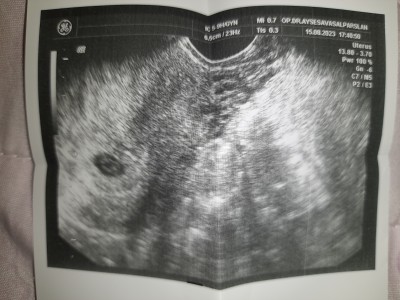

Bebek boyu mu kese boyumu bakarmisiniz 6.5 cm yaziyor

Gebelik haftası 7+1

Kese boyudur canım daha bebek çok minicik siz yeni mi gördünüz bebiş i bende şuan 6+3 um dün keseye baktı doktor kese yeni oluşmuş 10 gün sonra tekrrar gel dedi kalp atışına bebeğe bakalım dedi